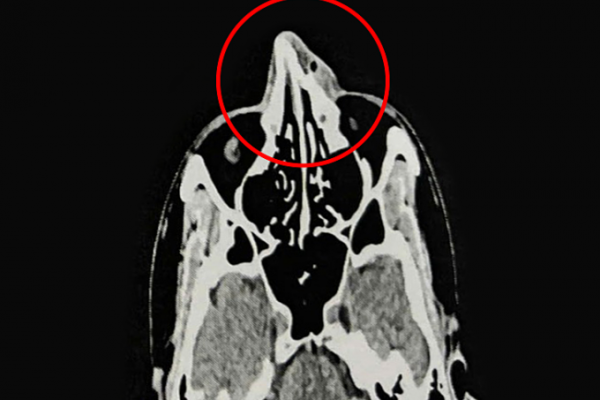

Anh Phi, một bệnh nhân gần đây, đã gặp phải chấn thương mũi trong một tai nạn, dẫn đến gãy xương mũi. Kết quả nội soi và chụp CT 128 lát cắt cho thấy anh bị gãy xương ở tháp mũi, phù nề tụ khí mô mềm vùng mũi, lệch vách ngăn và viêm mũi…